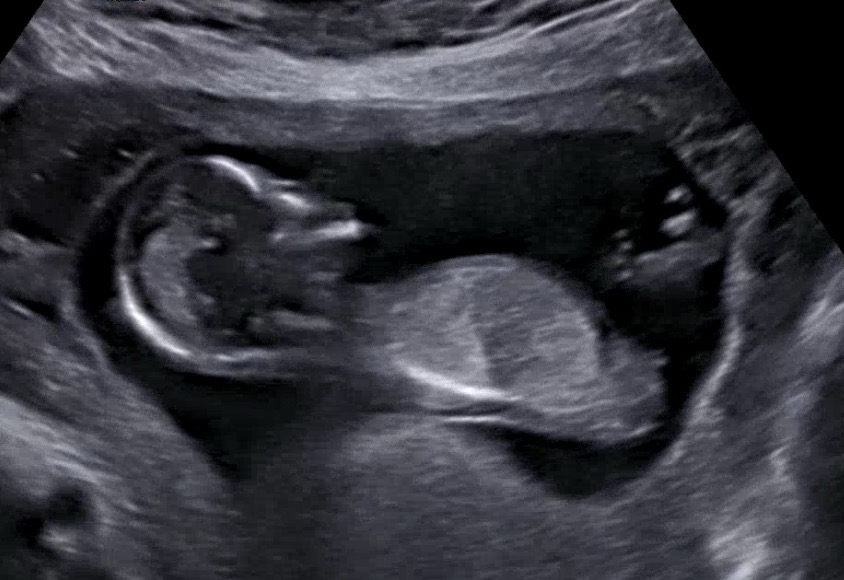

13주 각도법 좀 봐주실 천사분..!🙏

빌리 AI는 70프로 이상의 확률로 딸이라는데, 제 눈엔 돌기가 뭔가 솟아 보여서요ㅋㅋㅋㅋㅋ 선배맘님들께 고견을 여쭙습니다🙏